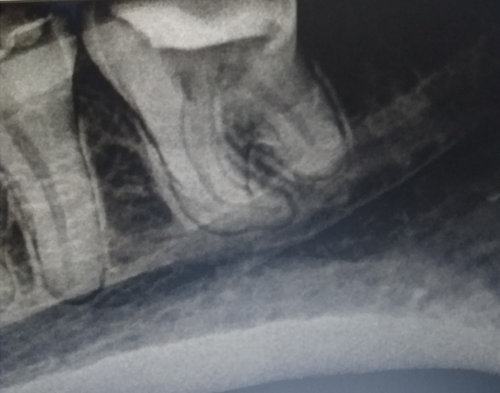

Здравствуйте! Обратилась к стоматологу для профилактического осмотра, для дальнейшего протезирования, два зуба запломбировали, а по поводу восьмого, зуба мудрости, снизу слева, стал вопрос — лечить или удалить. Врач объяснил мне, что этот зуб в жевательной функции не участвует, поэтому желательно сейчас удалить и не тратиться на его лечение. Так ли это? Или стоит его подлечить, а не удалять? Ведь удаленный зуб уже не вернуть. И участвуют ли эти зубы в протезировании, может ли он в дальнейшем пригодиться?

Ваш доктор прав, в основном для лечения каналов восьмых зубов не хватает доступа и в жевательной функции он действительно не участвует. И для протезирования в качестве опоры также такие зубы не используют.